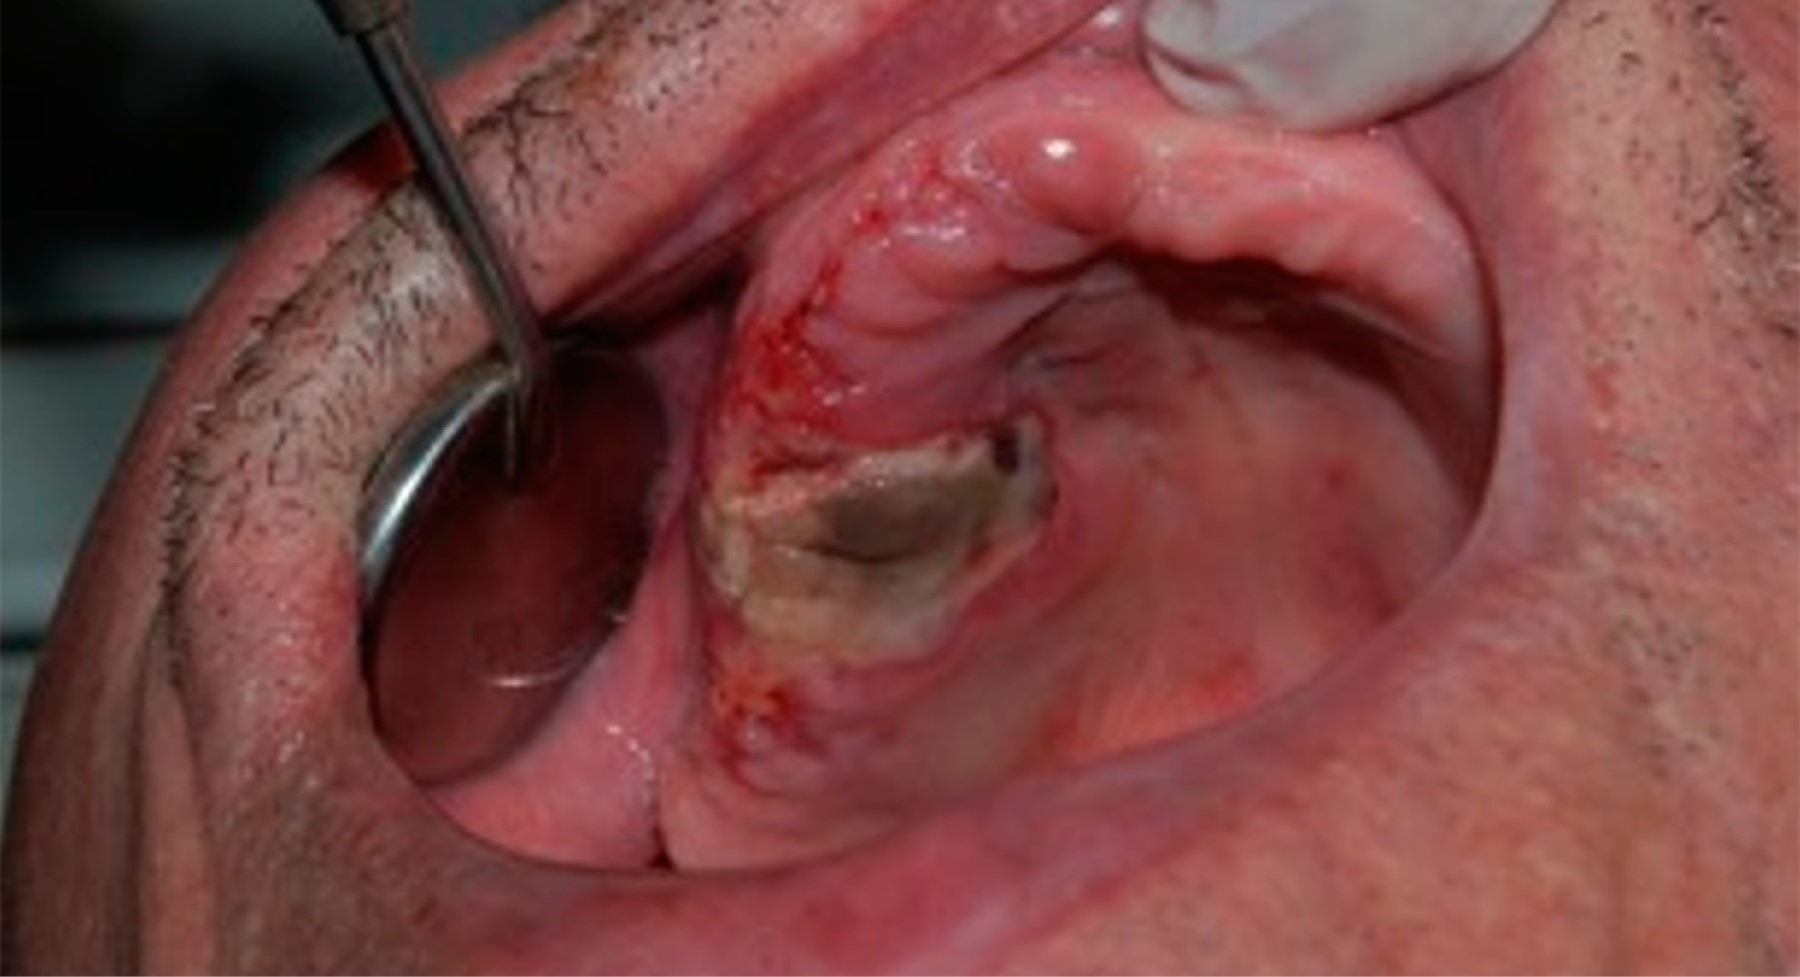

El leiomiosarcoma es un tipo de cáncer que se origina en las células musculares lisas del útero, el tracto gastrointestinal y otros tejidos blandos. La rara aparición del leiomiosarcoma en la cavidad oral se ha correlacionado con la escasez de estructuras musculares lisas en esta localización. Se trata de un tumor de tejidos blandos raro y agresivo que representa aproximadamente 5-10% de todos los sarcomas de tejidos blandos, y sólo 3% de estos tumores se producen en la región de la cabeza y el cuello. El diagnóstico diferencial puede ser problemático. El aspecto físico puede confundirse con afecciones no malignas. El diagnóstico diferencial clínico de la lesión incluye los tumores glandulares (adenoma pleomórfico, carcinoma mucoepidermoide y carcinoma adenoide quístico) y los tumores mesenquimales. Relatamos un caso de leiomiosarcoma maxilar en un paciente de 86 años que fue sometido a una resección tumoral y tuvo como complicación la necrosis casi completa del retallo quirúrgico. Gracias a la terapia con láser, logramos la curación completa del colgajo y el implante y la rehabilitación dental con carga inmediata.

Figura 3